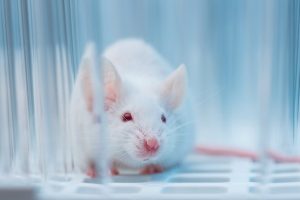

Esta dispersión resulta del bajo índice de refracción de la porción acuosa del tejido y del alto índice de refracción de sus componentes proteicos y lipídicos.